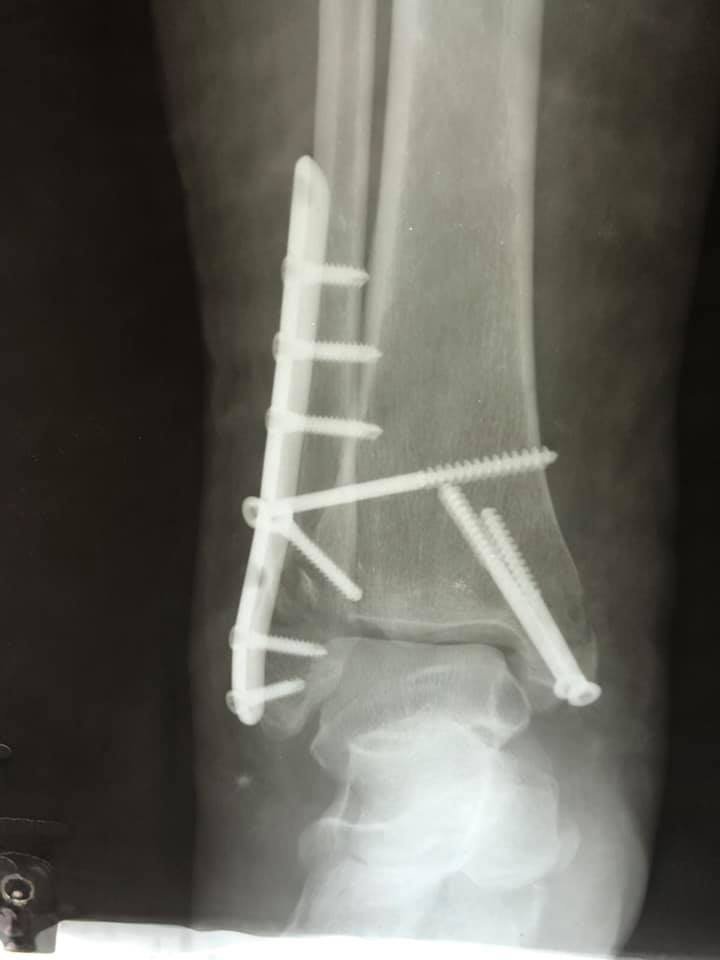

Пацієнтці виконали відкриту репозицію уламків з внутрішньою фіксацією. Операція пройшла успішно.

"В операційній працювали: лікар-ортопед-травматолог Родзь Тарас Яремович, анестезіолог Міщук Оксана Миколаївна, сестра медична операційна Магдюк Людмила Анатоліївна. Дякуємо нашим медикам за врятоване життя", - йдеться в дописі.